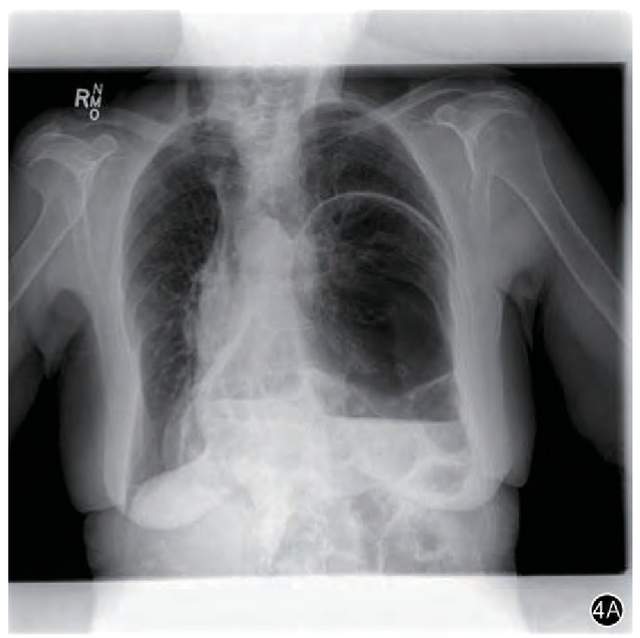

在一天发作时,让患者去拍了张胸片。

没想到,这张餐后的胸片一拍,还就把诊断给明确了。

胸片上看到,患者左侧胸腔里,出现了一大包空气和水的影像,医学上的话是可见“气液平(液气平)”。

原来,是胃泡“跑到”胸腔去了!

因为患者的“疝”是餐后发生的,所以早先没吃饭时拍的胸片可以是正常的。